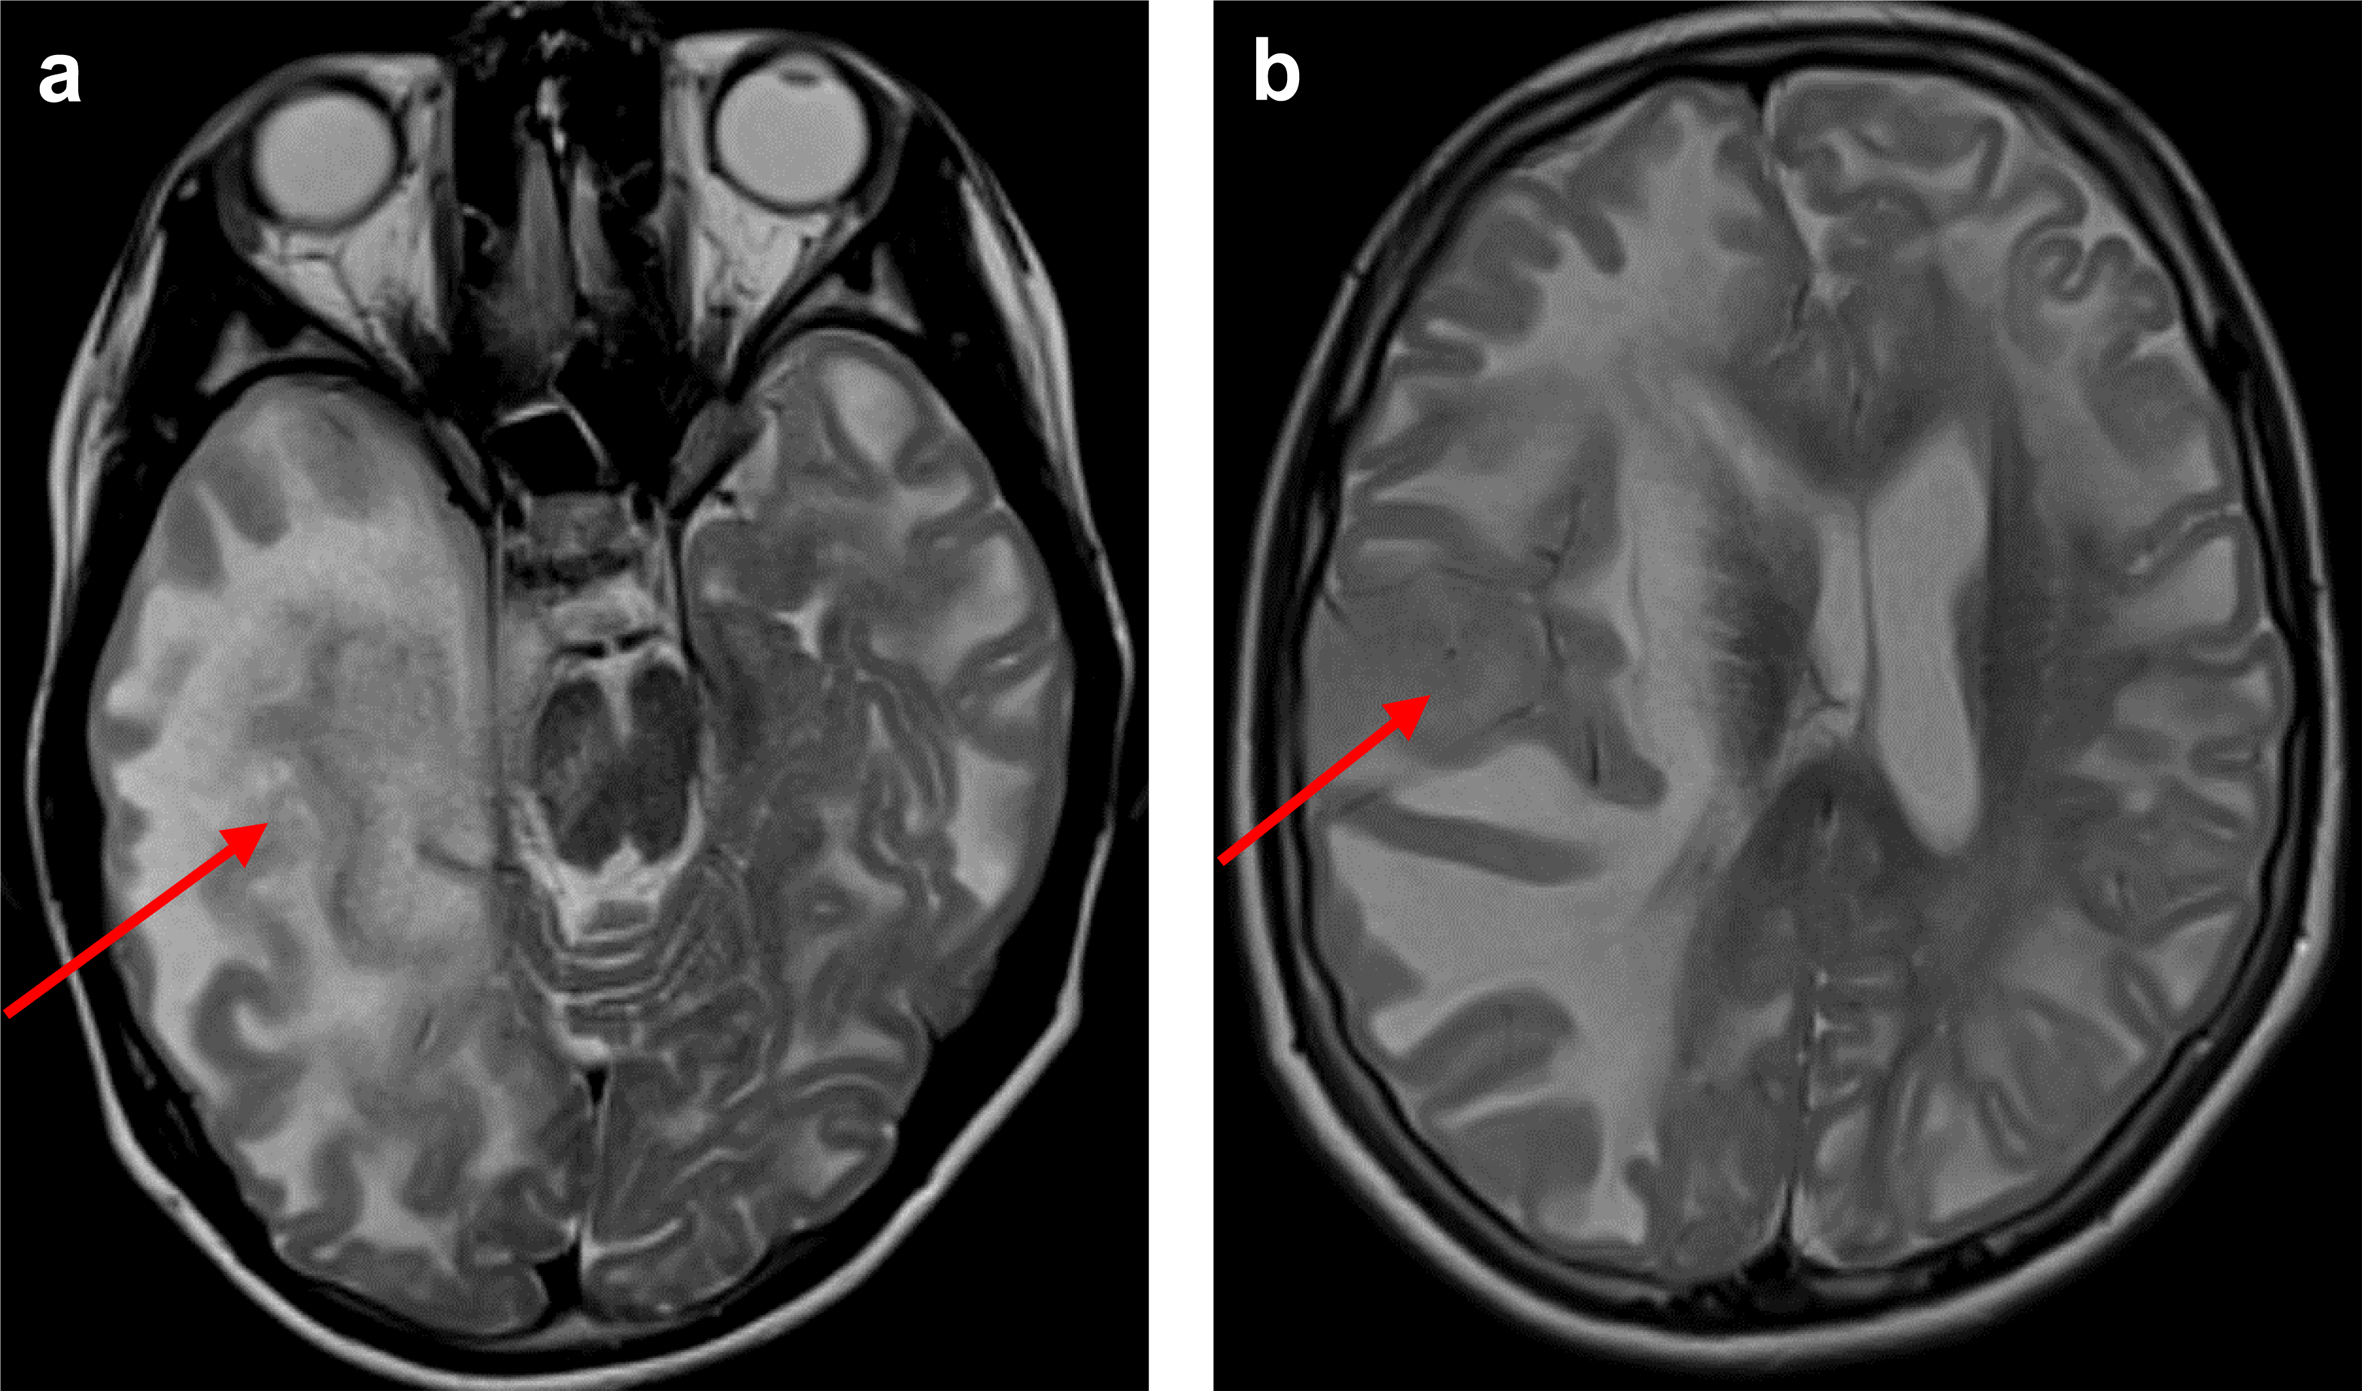

A 16-year-old girl, the sole child of a consanguineous couple, experienced a normal early development and could walk without support at 13 months. Speech development was delayed, and she exhibited mild motor coordination issues. At 5 years age, an MRI revealed extensive subcortical cerebral white matter abnormalities and signal abnormalities in the basal ganglia and dentate nuclei, characteristic of L-2-HGA. The diagnosis was confirmed through elevated urinary excretion of L-2-HG and the identification of a homozygous variant in the L2HGDH gene (L2HGDH(NM_024884.2): c.339T > A p.(Cys113*)).12 The parents were confirmed to be heterozygous for the same variant. Over the years, the patient developed moderate cognitive impairment and mild cerebellar ataxia. Starting at the age of 14, she experienced occasional epileptic seizures, treated with Valproate. MRI at the age of 14 years did not show evidence of tumor development. At age 16, a new MRI, prompted by a new-onset subtle left-sided central paresis, revealed an augmentation in T2 hyperintensity and swelling in most of the right cerebral hemisphere. The border between cortex and subcortical white matter was blurred, particularly medial in the temporal lobe, where the cortex was thickened and had a slightly increased T2 signal (Figure 1a). A similar tumorous area was identified in the right superior temporal gyrus (Figure 1b). Distinguishing pre-existing abnormal white matter related to L-2-HGA from the new abnormalities within the white matter was challenging. The signal abnormalities extended into the right thalamus, right cerebral peduncle, pons, and were accompanied by subfalcine herniation and a midline shift to the left (Figure 1a,b). Post-contrast scans did not reveal abnormal enhancement. Several small foci of diffusion restriction were present within the tumor. Based on the findings in serial MRI examinations a radiological diagnosis of a rapidly growing, likely high-grade glial tumor was made. A biopsy of the tumor was taken from the right temporal lobe near the superior temporal gyrus to confirm its nature.

Figure 1. Preoperative MRI. Axial T2-weighted MR images with the red arrows indicating a space occupying lesion in the medial part of the right temporal lobe (a) and in the right superior temporal gyrus (b, i.e. the location of the biopsy), accompanied by midline shift and brain herniation (transtentorial in a, subfalcine in b). Additionally, in both hemispheres T2 hyperintensity of the white matter is present, pathognomonic for L2-HGA.